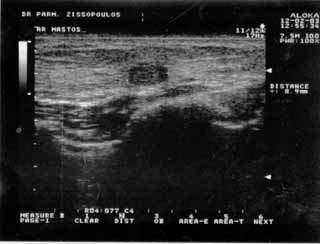

Για την καλλίτερη απόδοση της εξέτασης απαιτείται κεφαλή linear τουλάχιστον 7,5 ΜΗΖ. Ωστόσο και με κεφαλές 3,5 και 5 ΜΗΖ μπορεί κανείς να έχει καλά αποτελέσματα.

Oι τελευταίες 4 απεικονίσεις έγιναν με ειδικό για μαστό ηχοβολέα linear, εναλλασσομένης συχνότητος 7,5-10ΜΗΖ.